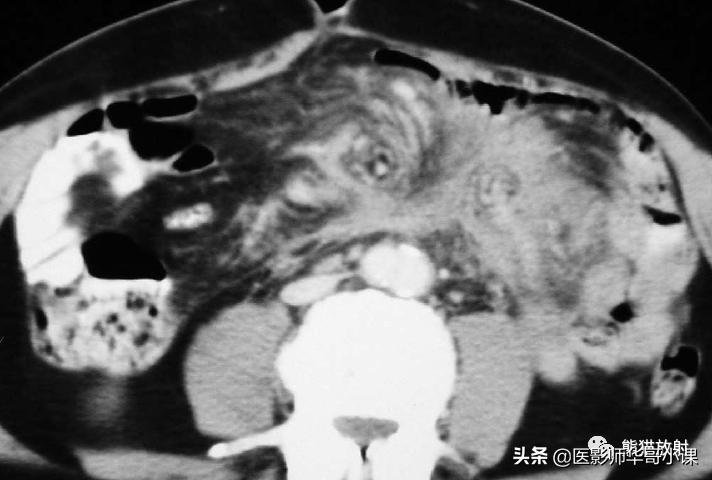

包虫病主要是感染细粒棘球绦虫所致。腹膜包虫病常常由于肝包虫病外伤或手术破裂而发生。 腹膜出现囊状占位性病变,囊壁薄,常有分隔 。腹膜种植时CT是首选检查方法(图)。边缘环形钙化具有提示诊断意义。

腹膜包虫病。增强CT显示一个大而多分隔的囊性腹膜肿块。囊内见子囊,多发分隔的蜂窝状表现,边缘钙化为其特征性表现。